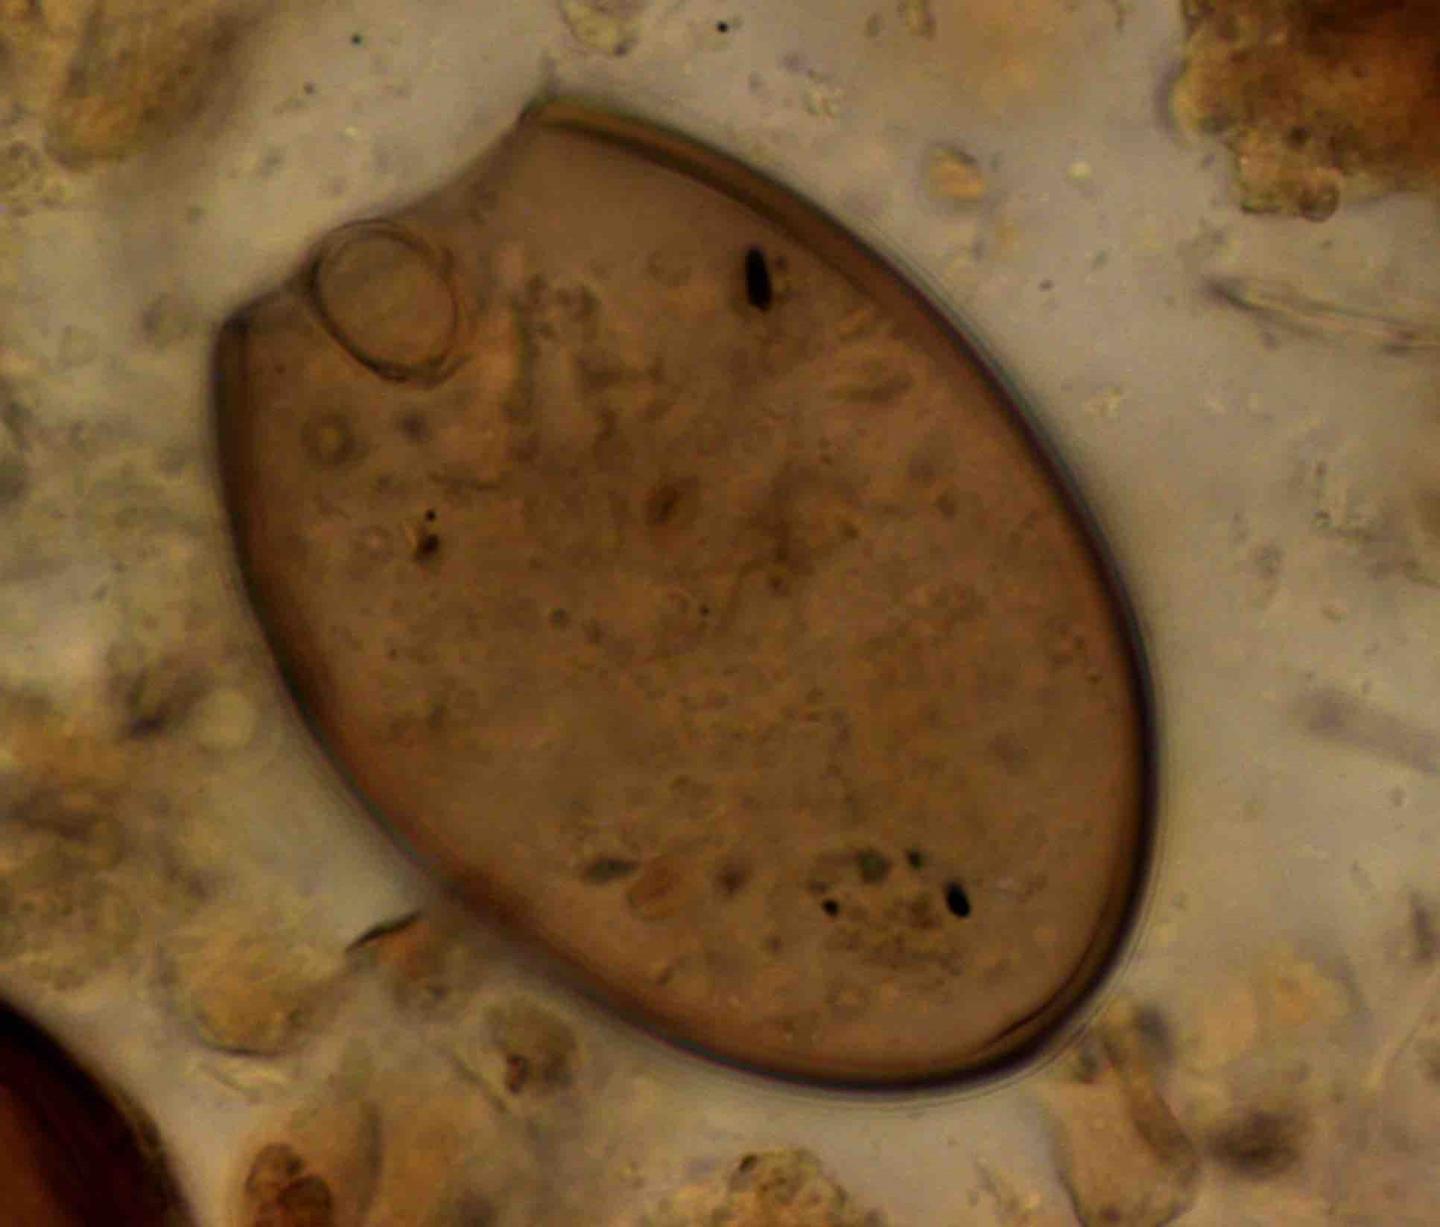

Microscopic Fish Tapeworm Egg [IMAGE] EurekAlert! Science News Releases

Microscopic Fish Tapeworm Egg [IMAGE] EurekAlert! Science News Releases Fish Tapeworm And Anaemia Fish tapeworm (diphyllobothrium latum) infection has been shown to be associated with vitamin b12 deficiency leading to. If the address matches a valid account an email will be sent to __email__ with instructions for resetting your password Diphyllobothriasis is the infection caused by d. Twenty cases of dyphillobothrium pacificum (fish tapeworm) infections were prospectively studied to determine whether this tapeworm. Fish Tapeworm And Anaemia.